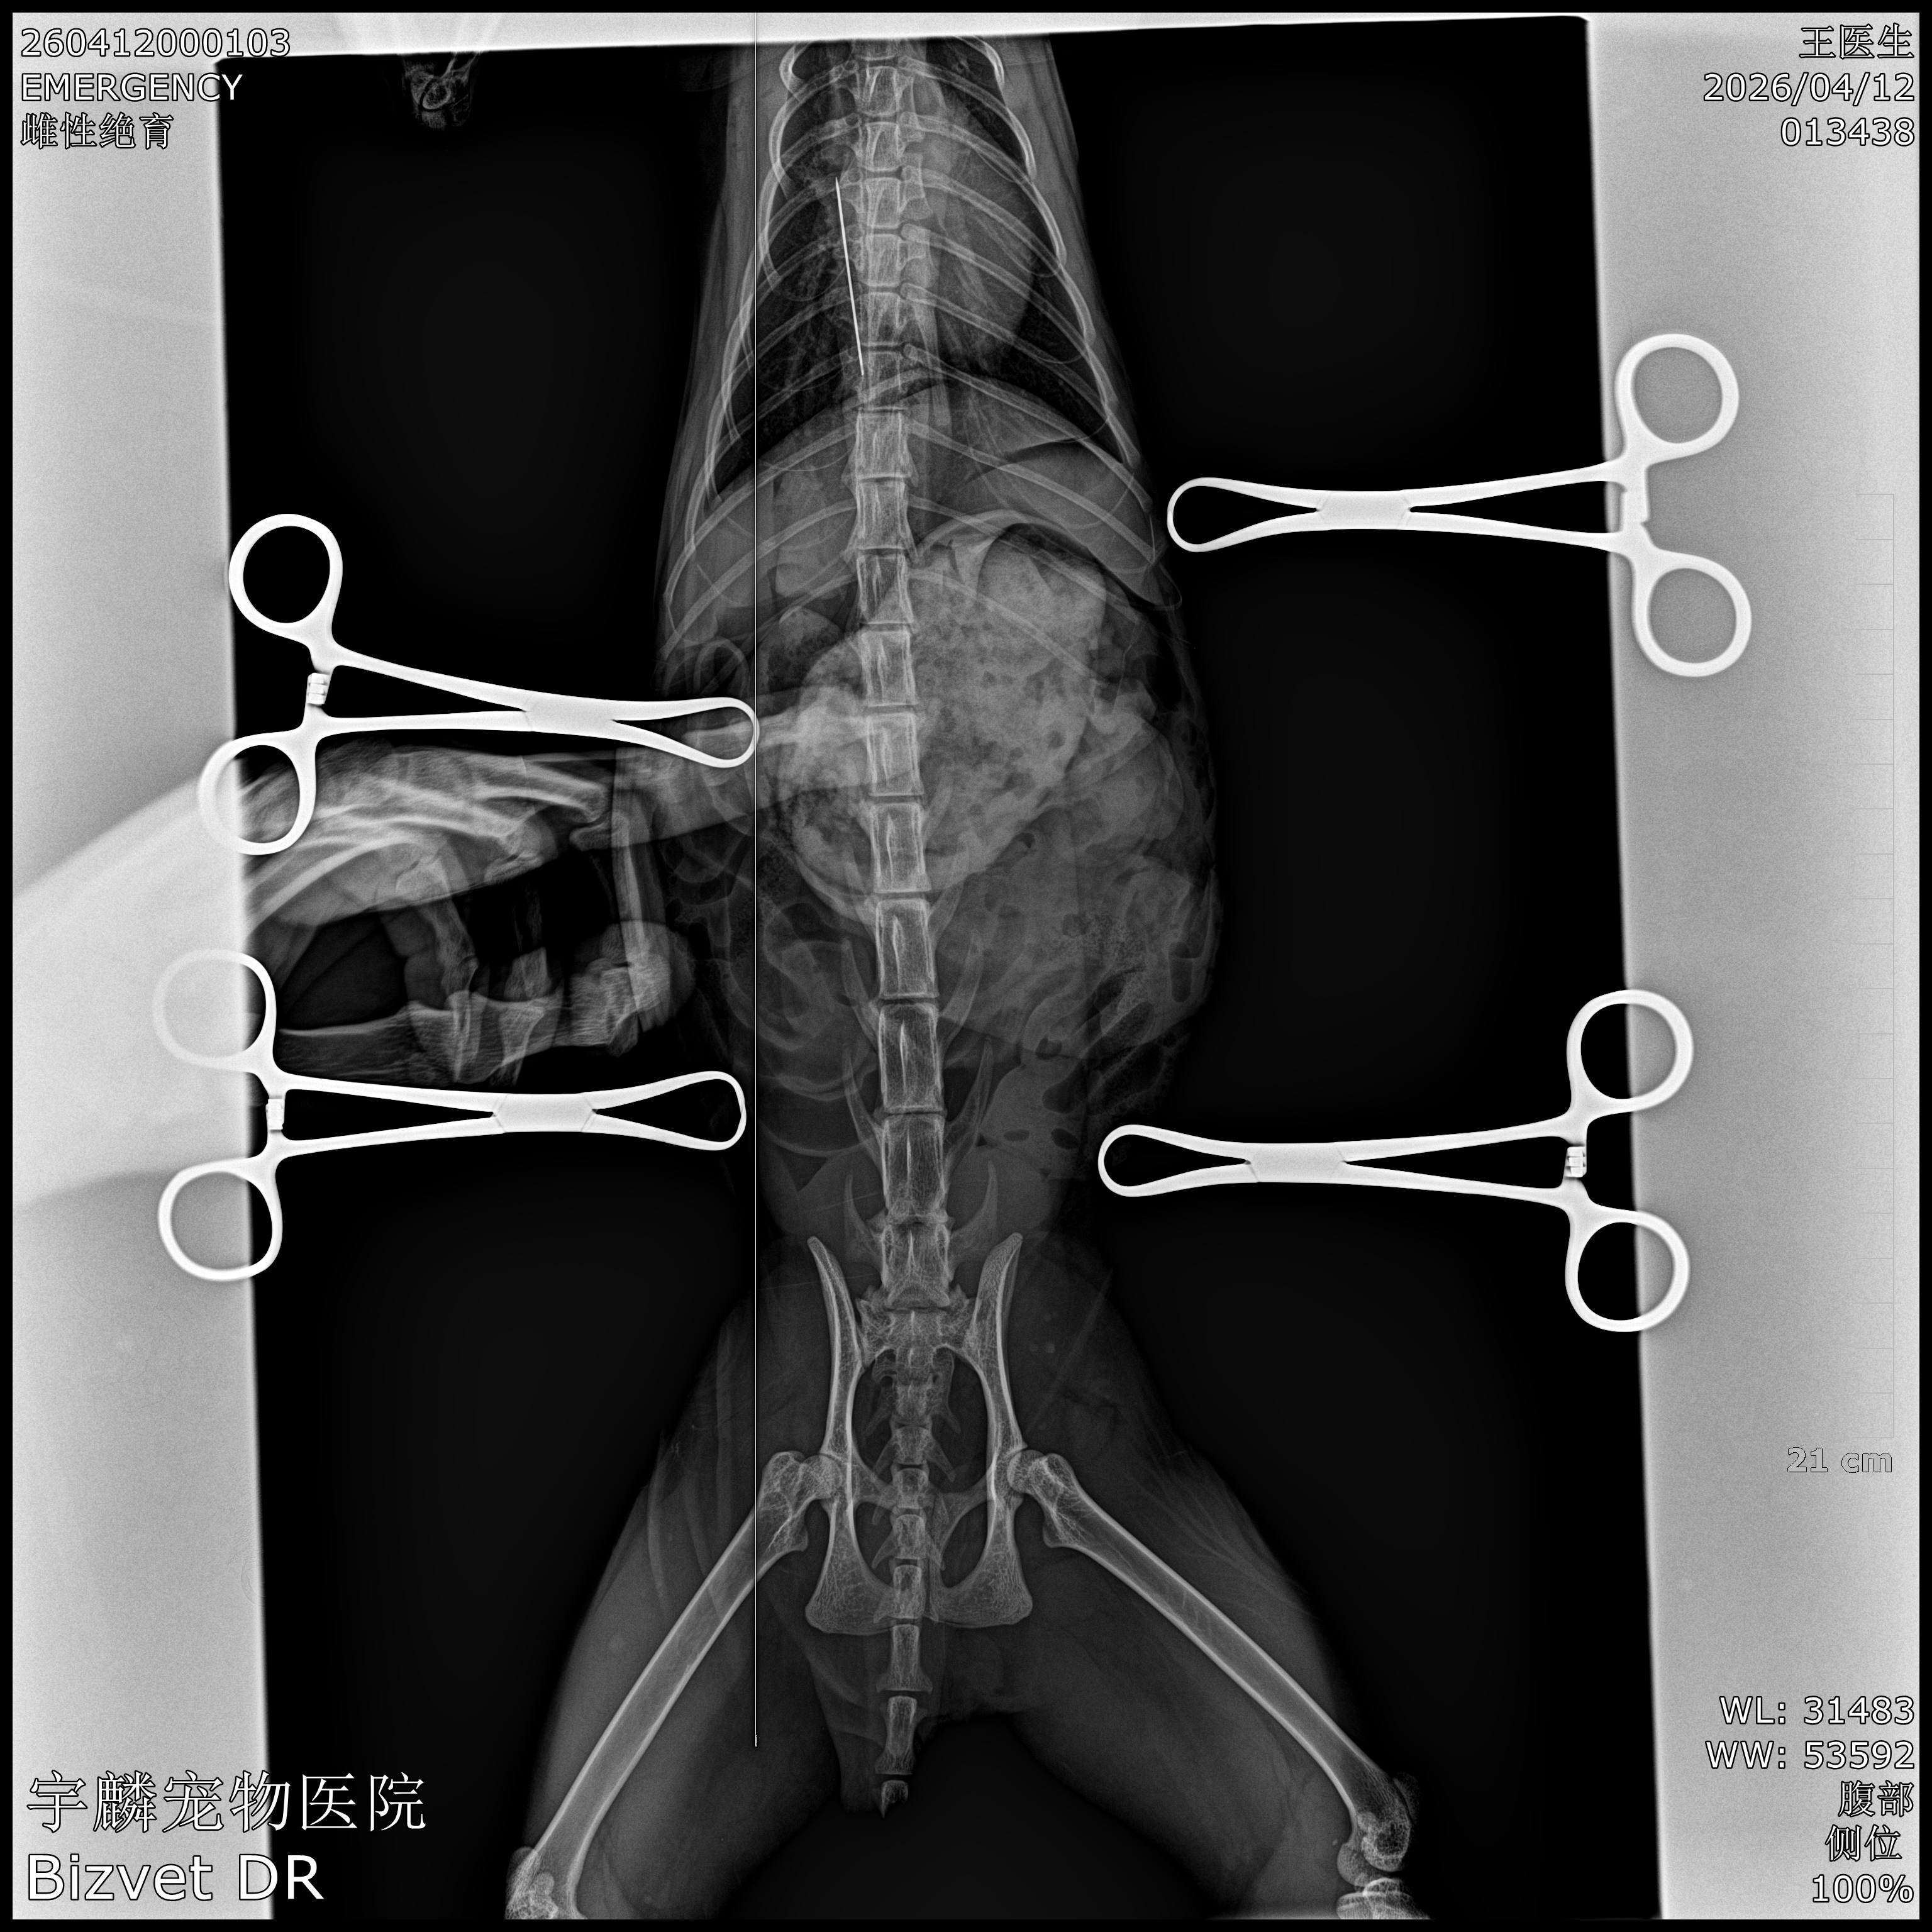

元宝趁主人不备,吞下了一枚尖锐的缝衣针。X光片上,那枚针静静躺在胃里,像一颗随时会引爆的定时炸弹——尖锐的针尖随时可能刺穿胃壁,游走进腹腔,造成致命的腹膜炎。

手术按计划进行。王医生凭借丰富的经验,精准定位到胃部……然而,探查的结果让所有人屏住了呼吸——

它并没有按术前影像显示的那样安静地待在胃里,而是在术中“逆行”反流进了食道。食道壁薄如蝉翼,紧邻心脏和大血管,稍有不慎,针尖就可能刺穿食道,造成纵隔感染或大出血,风险比胃内取针陡增数倍。

多年的临床经验让他迅速冷静下来:他小心翼翼地调整器械路径,避开重要脏器,以极稳的手法将那枚“不听话”的钢针从食道中完整取出。